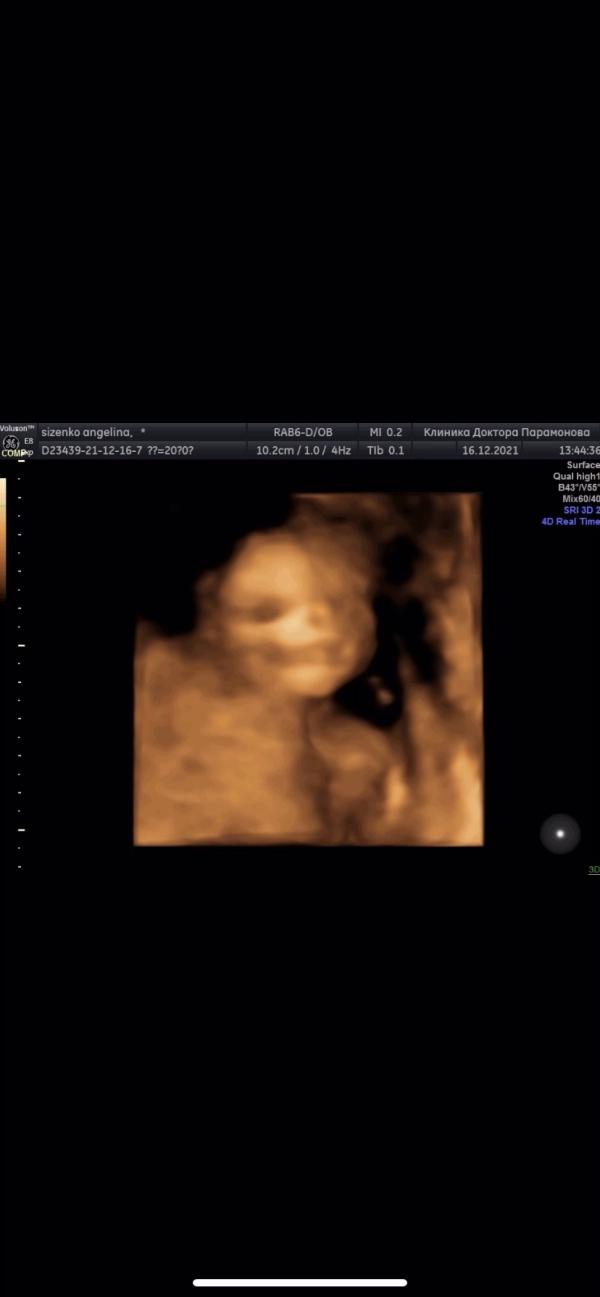

Сегодня прошли второй скрининг с мужем😍

Боже девочки, я на 7 небе от счастья✨С малышом всё хорошо, пол не хотел показывать, но врач вроде разглядела(будем шарик лопать в субботу)📨🥰головное придлежание🤰🏼одной ручкой носик чешет, а вторая ручка за головой😂как перед телевизором)))весим мы 305 грамм☺️

На узи улыбался нам, махал ручкой и язык показывал🔥